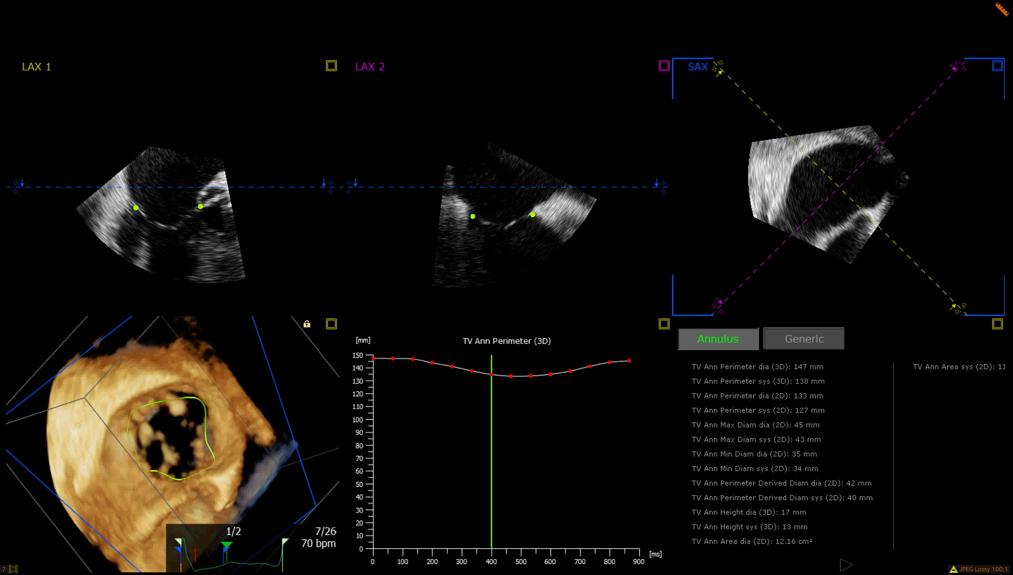

We retrospectively analyzed 19 patients with severe tricuspid regurgitation undergoing evaluation for TTVI who underwent both contrast-enhanced cardiac CT and TEE, with TEE performed a median of 93 days after CT (range: 0–247 days). Tricuspid annular dimensions were generated using an AI-powered 3D semiautomated analysis (3D Auto TV; Philips Ultrasound). CT annular measurements were independently performed in duplicate using the Aquarius iNtuition software. AI-generated echo measurements were visually reviewed and confirmed to ensure accuracy. Annular dimensions were measured in both diastole and systole using 2D and 3D perimeter-based diameter dimensions (perimeter/π) for both TEE and CT-derived measurements. Agreement between TEE and CT-derived dimensions was assessed with Pearson correlation coefficient. Inter-observer variability was assessed for CT-derived measurements of10 patients.

There was strong correlation between diastolic 2D TEE and CT dimensions (r = 0.564, p = 0.036). Intraclass correlation coefficient (ICC) analysis showed excellent reliability for 2D diastolic (ICC = 0.925) and 3D diastolic (ICC = 0.935) measurements. Systolic measurements showed slightly lower but strong agreement (2D ICC = 0.824; 3D ICC = 0.810). All ICC values were significant (p < 0.001). Interobserver variability for the CT scan measurements showed excellent agreement across all 2D and 3D tricuspid annulus measurements (ICC range: 0.916–0.969; all p < 0.001).